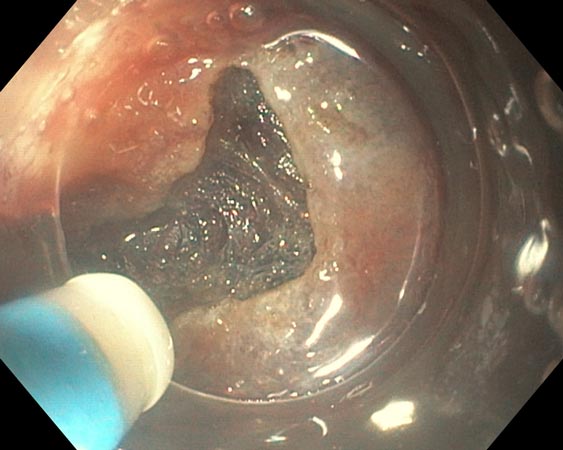

Возникшие в ходе 8 (38,1%) операций интраоперационные осложнения устранены эндоскопически. Серьёзное осложнение с нарушением герметичности стенки толстой кишки в ходе диссекции произошло у пациентки с латерально распространяющейся опухолью сигмовидной кишки. Перфоративное отверстие диаметром 0,3 см в зоне умеренного фиброза (F1) устранено эндоскопически сведением краёв дефекта клипсами в течение 5 мин с момента его обнаружения (рис. 7, 8).

Рис. 7. Перфоративное отверстие

Рис. 8. Клипирование перфорации